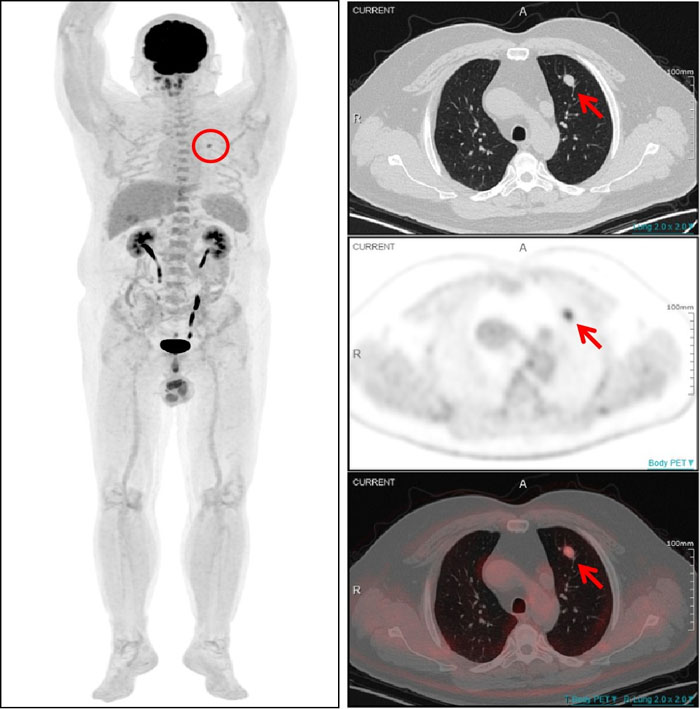

PET/CT显示:该结节伴明显异常葡萄糖高代谢(SUVmax4.5),为肺转移灶。

一名54岁男性患者曾在1年半前接受了左大腿脂肪肉瘤切除术,术后规律复查。一次常规CT检查发现其左肺上叶存在一个软组织结节,随后复查显示该结节有所增大,直径约为1.0cm。面对这一疑似转移的挑战,全景动态Total-body PET/CT 清晰显示左肺上叶结节伴明显异常葡萄糖高代谢,提示该结节为肺转移灶。基于检查结果,医生能够及时为患者制定更加个体化的治疗方案。对该患者的诊断,彰显了全景动态Total-body PET/CT 在癌症诊断领域的非凡实力。